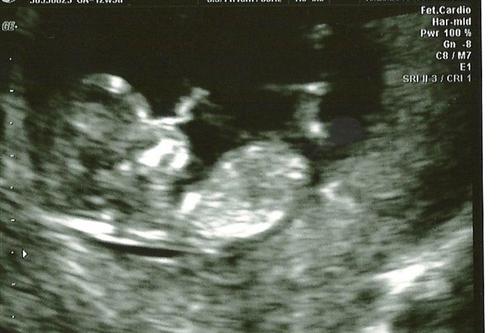

Our baby

kristenbrown

10/28/10